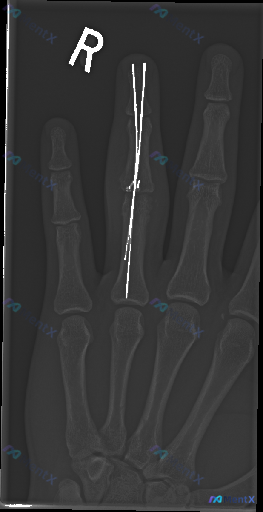

- 影像学是右手指正位X光

- 明确看到右手中指近节指骨有金属内固定物(疑似克氏针)

- 除了金属伪影遮挡的区域,其余各指骨皮质连续,关节对位也还行,骨密度、软组织也没说有特别典型的急性异常

- 但核心矛盾点:病例提示存在“异常”(Abnormality present)